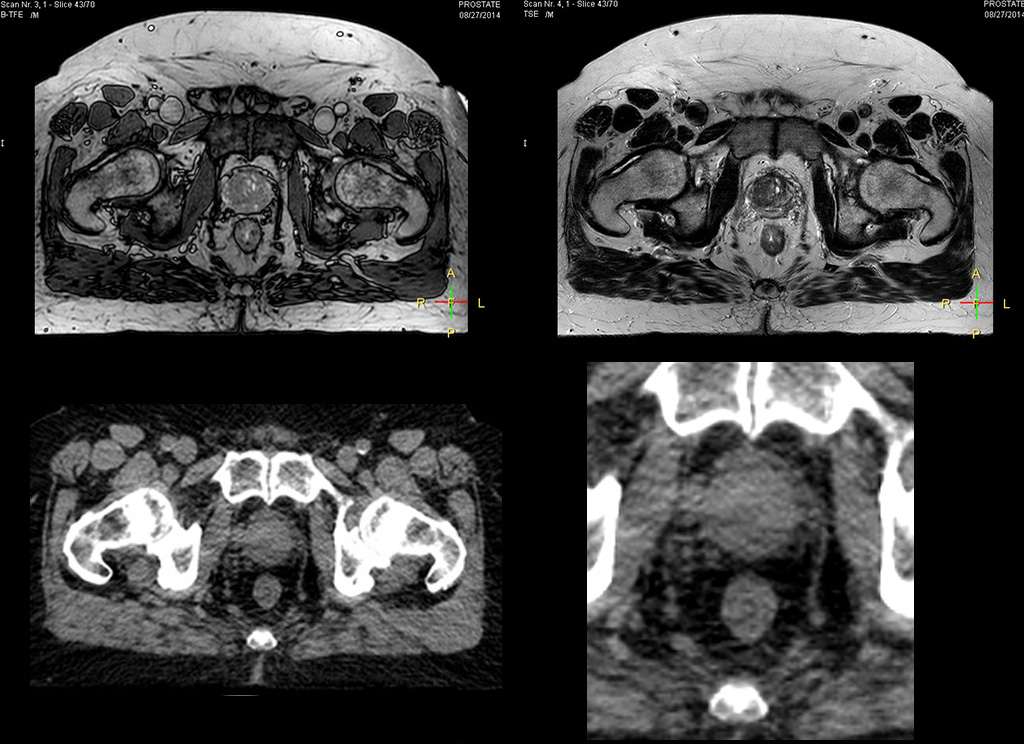

“The biggest problem for CT-based planning, especially in prostate, is you can’t see the cancer very well,” says Dr. Stevens. “On CT it can be quite challenging to see the edge of the prostate especially at the apex. When the edge of the prostate can’t be delineated well on CT, radiation oncologists will increase their margins a little bit so they don’t miss it, but that can also increase toxicity.” “Using MR, the prostate is well delineated. We quickly see the edges of cancerous tumors like in prostate cancer, and as normal structures can be defined, we can optimize the treatment plan to protect these organs and their normal function. This can potentially improve the outcome. And it improves workflow as well. We can contour more quickly, confident that the tumor is going to be in the field.” “The Ingenia 3.0T MR scanner provides high resolution allowing us to make scans fast for the patients. It also gives the potential to include methods like MR spectroscopy and diffusion weighted Imaging, which we’re in the process of doing right now,” Dr. Stevens adds.

“There are some general challenges in RT imaging – even with CT – such as imaging geometry and positioning accuracy. Positioning is extremely important in RT, because we need reproducibility between imaging and treatment position. We also need accurate geometry so we can be sure our treatment plan is properly delivered during the treatment,” says Dr Yan. “The Ingenia MR-RT configuration includes an external laser positioning system for patient alignment and a flat tabletop for imaging the patient in treatment position. Ingenia MR-RT also came with a special QA package for regular monitoring of precision. Our Ingenia 3.0T scanner achieves good geometric accuracy – within a millimeter for most patients – and the phantom measurement is even better,” he adds. “Ingenia’s wide 70 cm bore is valuable to easily accommodate immobilization devices needed in RT,” says Dr. Stevens. “With a small bore MR scanner you can’t get the RT immobilization devices into the scanner properly; the large bore makes it easy to image patients in their immobilization device.”

“When a patient registers, first CT simulation and MR simulation are done, followed by CT-MR registration on Pinnacle3. Then the target and normal organ delineation is performed on MR images. Meanwhile we create a reference CT image for online treatment and localization correction. During the treatment phase we can perform additional MRI scans to visualize the anatomy changes and create an adaptive plan. This plan basically adapts the treatment plan to the changes.” “Along with its great benefits, MR has introduced some new challenges,” Dr. Stevens says. “Radiation therapy teams generally have no experience with MR. The Philips training helped us to implement fully the things we can do with the Ingenia MR-RT system. So the training, as well as having a good MR physicist, is critical.”